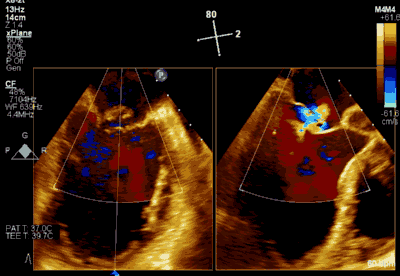

▲ 术前超声检查显示重度二尖瓣反流

患者为73岁老年男性,既往合并冠心病、持续性心房颤动、肾功能不全病史,此次主诉“反复胸闷气促3月余”入院。诊断:心脏瓣膜病 二尖瓣脱垂伴重度关闭不全 心功能Ⅲ级(NYHA分级)。术前经胸超声心动图示:左房扩大,二尖瓣前后叶冗长、P2脱垂合并重度反流(Type II类 DMR/MR4+)。心脏测值:LA 54 x 58mm,LVD 60mm,EF% 60%,PASP 36mmHg。经食管超声心动图示:二尖瓣环左右径38mm,反流束缩流颈宽度为8.5mm,EROA 0.72cm2(PISA),舒张期二尖瓣口平均跨瓣压差2mmHg。